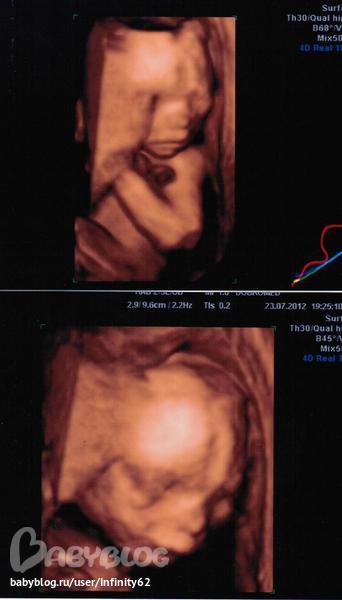

Решила написать свой отчетик о пролетевшей половине после того, как сходим на 3D УЗИ, чтобы и с фотками было, да и срок нам ставили в последний раз на недельку меньше.

Мне сложно считать по М, т.к. был сбой именно в этом цикле) Поэтому всем врачам говорю, что М наступили 25.02.2012, чтобы не заморачиваться и не объяснять, что О была поздняя. Итак, по М срок - 21 нед. и 2 д. По УЗИ вчера подтвердили развитие на 21 нед.

Вес - 416 гр. А вот про рост в заключении не написали ничего(

В пузике у нас живет маленькая принцесса! Ура-Ура! Можно начинать закупаться! Все УЗИ закидывала ноги на голову и пыталась закрываться ручками) Но мы ее отловили для фото)